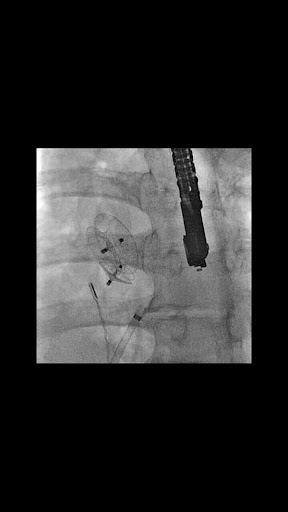

CARDIO3® Atlas of Interventional Cardiology is a CARDIO3®INVASIVE project – reference/learning tool for cardiologists, cardiac surgeons, internists, other physicians evaluating interventional images in cardiology.

B. Coronary interventions

- 300 annotated videos (September 2011) and growing